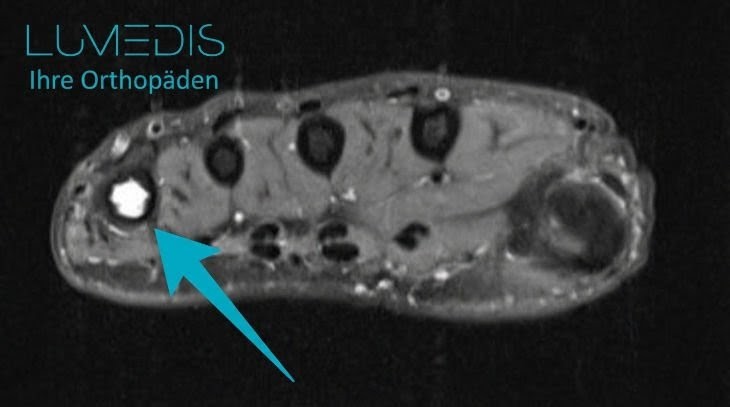

Zyste Fußknochen (türkiser Pfeil)